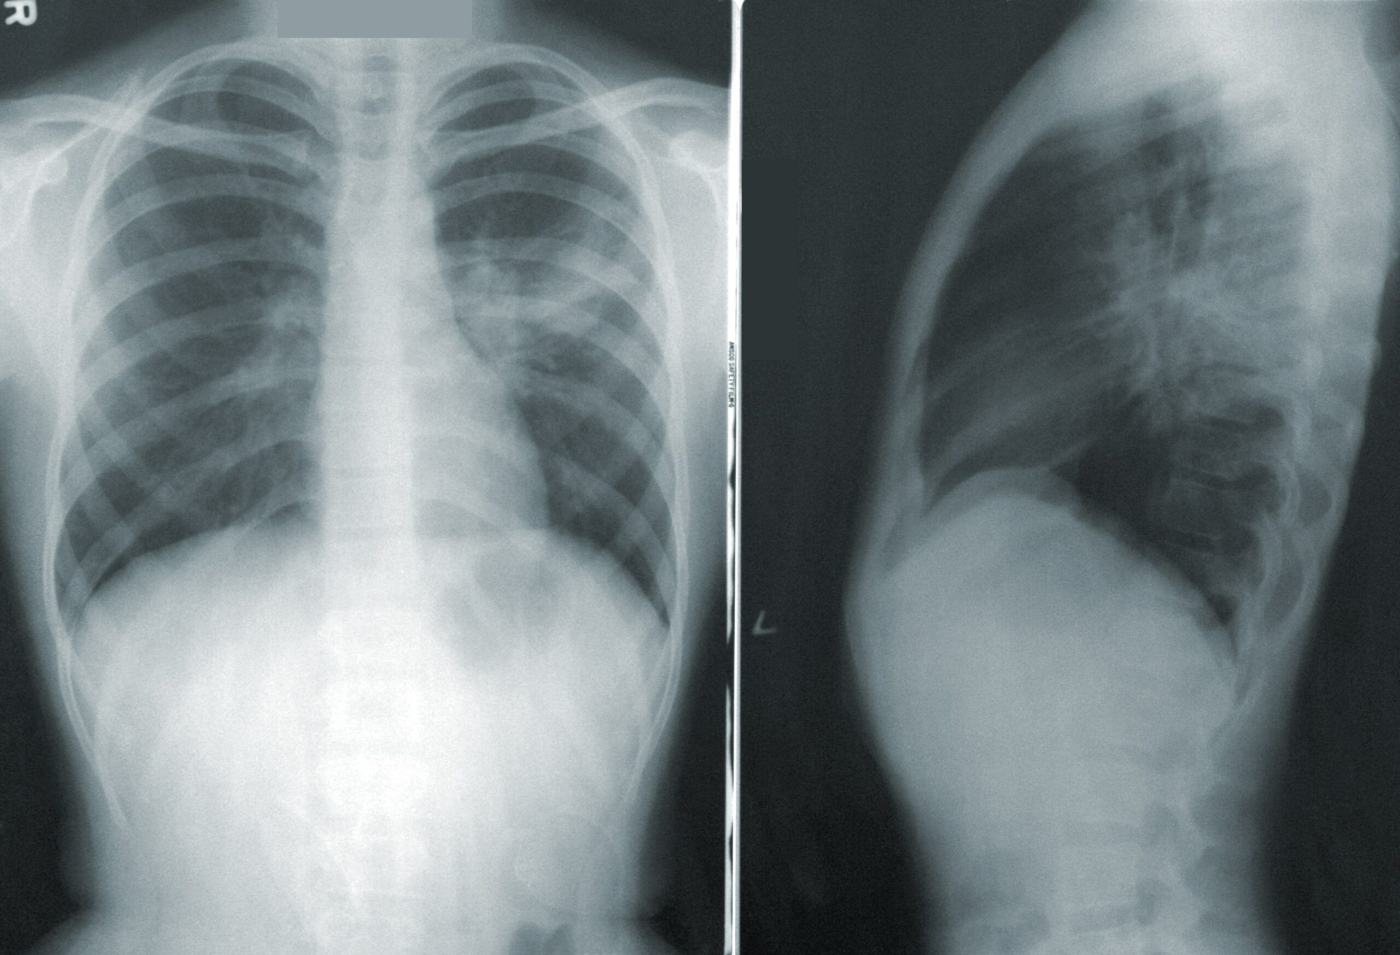

Sedangkan, pneumonia adalah penyakit infeksi yang menyebabkan peradangan dan pembengkakan pada kantung udara paru-paru atau alveolus. Pneumonia juga kerap disebut paru-paru basah.

Peradangan membuat kantung udara terisi dengan cairan atau nanah dan menimbulkan gejala seperti batuk, sesak napas, demam, dan kedinginan.